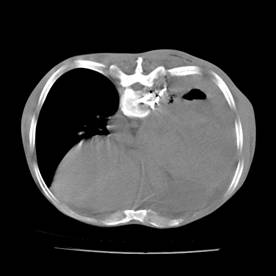

典型病例1:患者鞠xx,女,68岁,住院号:488141,因左胸痛1月余入院。2015年3月31日胸部增强CT示:左肺下叶2.5cmx2.8cm占位,左侧第三前肋骨溶骨性转移、形成厚约3cm肿块,左侧腋窝淋巴结2.1cmx4.1cm及前纵膈淋巴结转移。患者于2015年4月1日经CT引导下穿刺活检、病理证实为左肺下叶腺癌。于2015年4月5日对其采用125I放射性粒子置入治疗。治疗3个月随访,患者胸痛缓解,左肺下叶原发病灶消失,粒子聚集;左侧第三前肋骨基本恢复正常形态;前纵膈淋巴结消失,粒子聚集;左侧腋窝淋巴结缩小2/3。目前患者生活质量良好,可从事一般家务劳动。

术前CT片: